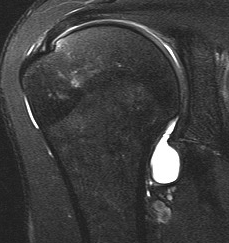

MRI

Normal humeral insertion of IGHL on left, HAGL with discontinuity of J sign on right